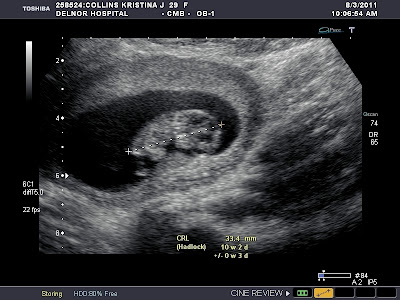

Tuesday, I had a little scare -- a small amount of bleeding, but since, up to this point, I have had none, I was very, very nervous and more than a little upset.  On Wednesday, I had an ultrasound to check on things (I think this was more for my peace of mind than anything), and our little peanut is doing just great!  It actually looks like a baby now and I got to see it kicking its little legs and moving its arms.  It was so relieving!  It is now about 33 mm long and had a heart rate of 160.  It has grown so much!  Just think, at 7 weeks, it was only 7 mm!

You can see its little face and its arms and legs!!  I can't wait until I can call it something other than "it."